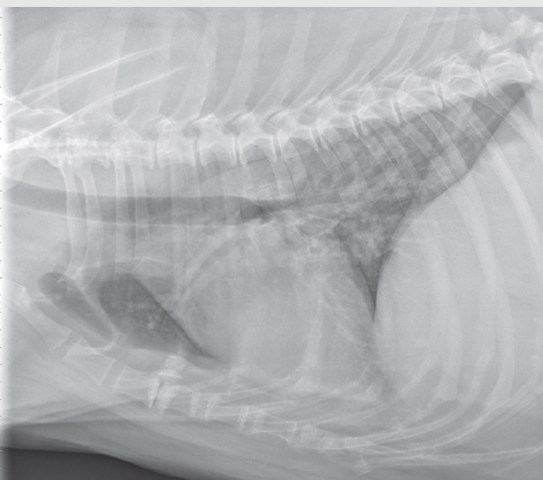

Total situs inversus

Heart is located towards the right side of thorax

Dextrocardia

Partial situs inversus occurs but heart is in normal position

Levocardia

Heart is positioned towards right side of thorax

Dextroversion

Mirror image of the thoracic and abdominal organs

Situs inversus

Normal position of organs in the thoracic and abdominal regions

Situs solitus

Heart is predominantly in the right thorax with cardiac apex pointing towards the right

May be due to cardiac diseases with left heart enlargement and mediastinal shift

Dextroposition

Heart is located in a normal left-sided position

Levoposition